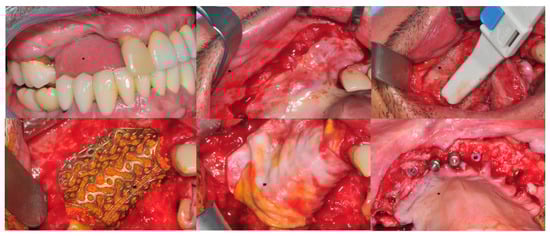

Figure 2.

CBR involving upper jaws. Top line, from left to right: initial clinical situation, flap design, bone refreshing. Bottom line from left to right: CBR in place, covering of it with a resorbable membrane, implanting of insertion after grid removal and clinical evaluation of the bone quality obtained.

Figure 3.

Occlusal and frontal intra-oral aspects of the immediate loaded full arch prosthesis. (Left): occlusal view. (Right): front view.